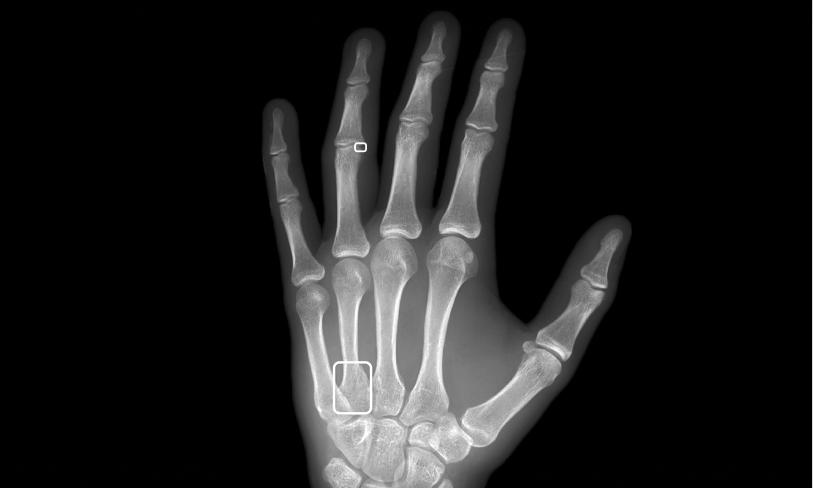

Opportunistic screen for low bone materials density